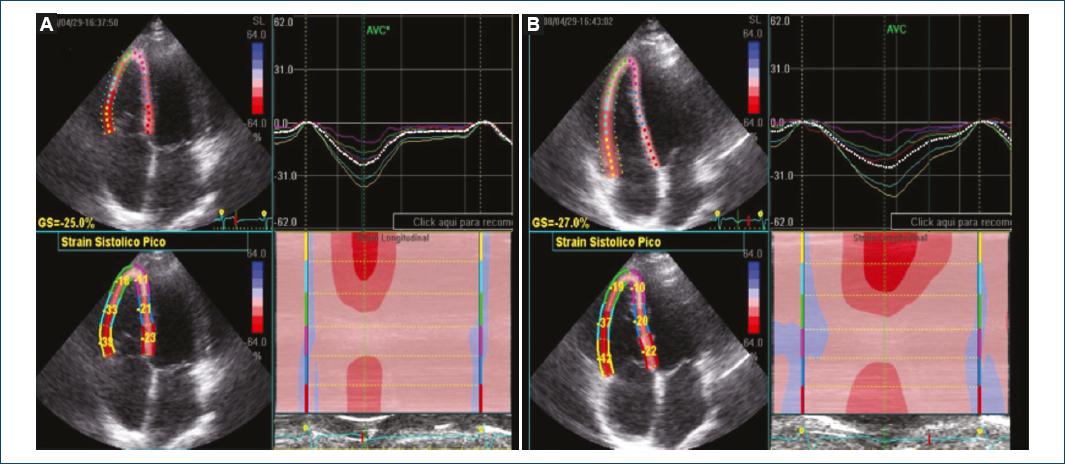

Thirty-one subjects were analyzed, 16 men and 15 women with ages ranging from 16 to 53 years. GLS and SLS behavior before and after leg elevation to 45° is shown in table 1 and figure 1; a box and whisker plot shows mean differences and the distribution is observed to be larger (i.e., higher dispersion), and there is also a positive bias for the subjects at rest (Fig. 2). The intra-class correlation coefficient was calculated: 0.773, with a 95% confidence interval (CI) of 0.534-0.890; p < 0.001.

2D STE measures RV GLS and SLS with a four-chamber approach. We measured it in healthy subjects at rest and with position changes (leg elevation to 45°), a maneuver that was used with the purpose to increase preload. There are no previous studies on RV performing this maneuver. There are studies on LV where STE-observed longitudinal and circumferential strain has been calculated to be affected by acute changes in saline infusion-induced preload16. We obtained significant GLS and SLS differences in the basal and mid-RV free-wall segment. We found that the strain is more negative with leg elevation to 45°, which supports that the greater the stretching of the myocardial fiber by increasing the preload, the more negative the generated deformation, indicating that there is a greater shortening of the fiber, and this method can measure those differences.